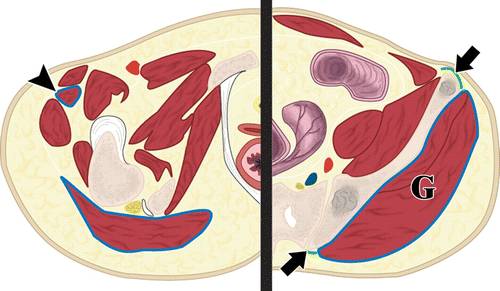

对于主要的骨损伤,如果可能的话,避免向后穿过臀肌和股直肌前方(图6)。切除臀部肌肉与保留肢体的手术后的不良结果相关,因为这些肌肉在手术后提供了相当大比例的功能。通过髂骨的前方或后方途径避免臀肌组织(图7))。如果病变是可疑的转移,可以使用硬件稳定而不是切除。因此,可以选择最短路径(图8))。

6 -髂骨水平(右)和下耻骨支(左)的骨盆插图。

必须避免臀肌群(G)和股直肌(箭头)。理想的方法是直接进入髂骨(箭头),无论是前或后